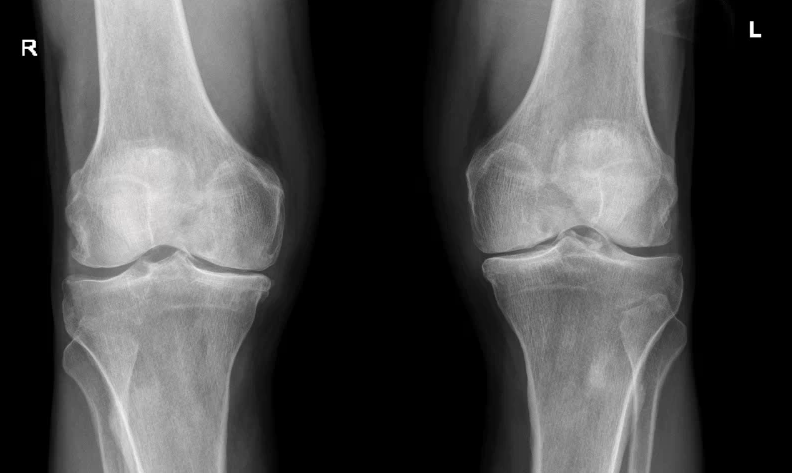

TAME works best for patients with moderate osteoarthritis, corresponding to Kellgren-Lawrence grades 2 and 3 on X-ray. At this stage, inflammatory processes are active and responsive to treatment while structural damage has not yet progressed to end-stage disease. Success rates in these patients are highest, with many experiencing significant and lasting pain reduction and improved function.

Patients with more advanced disease (KL grade 4) may still benefit, though the success rate is lower. At this stage, mechanical factors such as bone-on-bone contact play a larger role in generating pain, and inflammation — while still present — is no longer the dominant driver. Even so, addressing the inflammatory component can provide meaningful improvement for some patients.

Early-stage osteoarthritis (KL grade 1) does not typically warrant TAME, as conservative management remains appropriate.

Frontal bilateral knee X-ray showing moderate osteoarthritis on both sides.